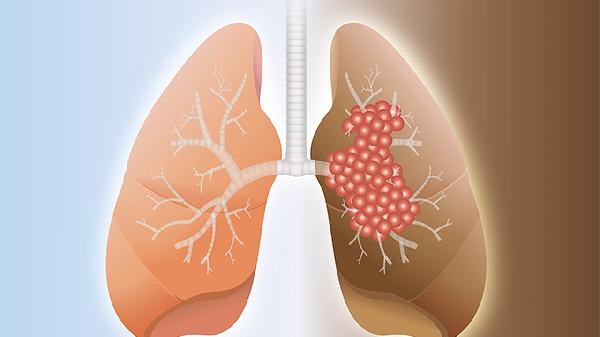

肺癌放疗后胸疼可能与放射性肺炎、放射性食管炎、胸膜反应、肋间神经损伤、肿瘤进展等因素有关,可通过药物镇痛、物理治疗、营养支持等方式缓解。放疗是肺癌治疗的常见手段,但可能对周围正常组织造成一定影响。